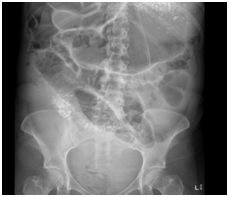

Case patient developed two episodes of large (200ml) green vomit 24hours after the caesarean section. On review, her epigastria pain improved after the delivery but nausea remained. The vomit was brought on by food. Bowel sound was absent on abdominal examination. The abdomen was generally soft and appropriately tender to what one would expect soon after a caesarean operation. A plain abdominal radiograph (AXR) revealed dilated loops of small bowel indicating post-operative ileus. Input from the general surgeons was sought on day two post-op which recommended nasogastric tube (NGT) decompression with free drainage. Chest radiograph (CXR) was ordered to confirm correct position of the NGT. Interestingly, the NGT still remained coiled in the oesophagus on the second CXR see Figure 1 after being repositioned. Despite of this, the NGT was draining stomach content freely and a decision was made not to subject the functional NGT from further repositioning. Case patient’s symptoms did not improve after 24 hours of drainage, therefore a repeat AXR with gastrograffin study see Figure 2 was organised which suggested the possibility of a small bowel obstruction. An abdominal computed tomography (CT) was arranged to confirm and locate the small bowel obstruction. It showed the presence of abdominal content in the right sided chest through a diaphragmatic defect see Figure 3. A right sided non-strangulated diagrammatic hernia was diagnosed. The general surgeons performed an emergency laparoscopic right sided diaphragmatic hernia repair and returned the incarcerated bowel to the abdomen. Upon direct visualisation, 20cm of terminal ileum was herniated through a 6cm defect on the right diaphragm. The defect was approximated and sutured with four interrupted size 0 monofilament nylon sutures. The case patient recovered well after the operation and was discharged home 5 days after with a healthy baby girl.

Figure 1 repeat CXR which showed coiling of NGT in the oesophagus despite reposition was attempted. Pleural effusion is also seen in the right lung base.